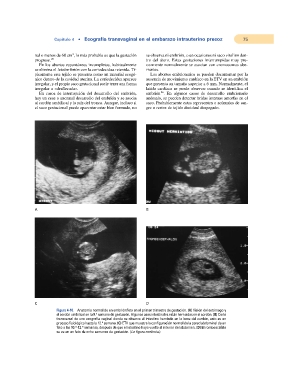

Figura 4-10. Anatomía normal de un embrión/feto en el primer trimestre de gestación. (A) Visión del estómago y

el cordón umbilical en la 9.a semana de gestación. Algunas asas intestinales están herniadas en el cordón. (B) Corte

transversal de una ecografía vaginal donde se observa el intestino herniado en la base del cordón, esto es un

proceso fisiológico hasta la 12.a semana. (C) ETV que muestra la configuración normal de la pared abdominal de un

feto a las 10.a-12.a semanas, después de que el intestino haya vuelto al interior del abdomen. (D) El rombencéfalo

se ve en un feto de ocho semanas de gestación. (La figura continúa.)